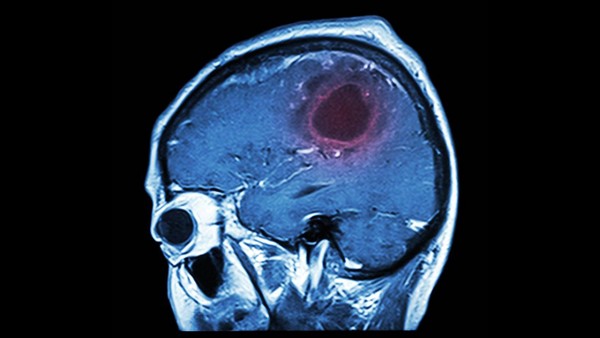

在癫痫发作时,很多癫痫患儿,之所以有,说不出话的情况。除了语言的功能,发育不够完善之外,还跟癫痫的发病,癫痫患儿的大脑中枢,发生异常“短路”等,有十分密切的关系。会出现类似多动症的反应。这种反应的征兆,像是坐立不稳,急躁、狂暴、有攻击性,出现欲求不满的愤怒、急躁不安等,其实是癫痫患儿癫痫发作的征兆。

癫痫失语的一般概念首先,我们要知道的是,癫痫失语症的出现,是癫痫病患者,多种因素的综合结果。医学上,将癫痫失语症,进行了准确的定义。获得性癫痫失语综合征,是癫痫失语症,最为正是的称呼。癫痫患儿,失语、语塞的发生,有时会有单音节,比如“啊”、“呀”等情况。这种发声,虽然并不多见。可出现恶原因,却是生理的反应,而不是自主的问题。